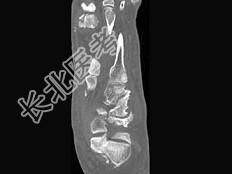

- 单项选择题男,56岁, 踝关节肿胀,有糖尿病史, 结合图像,最可能的诊断是 ( )

A、创伤性关节炎

B、退行性关节病

C、痛风

D、类风湿关节炎

E、神经性关节病